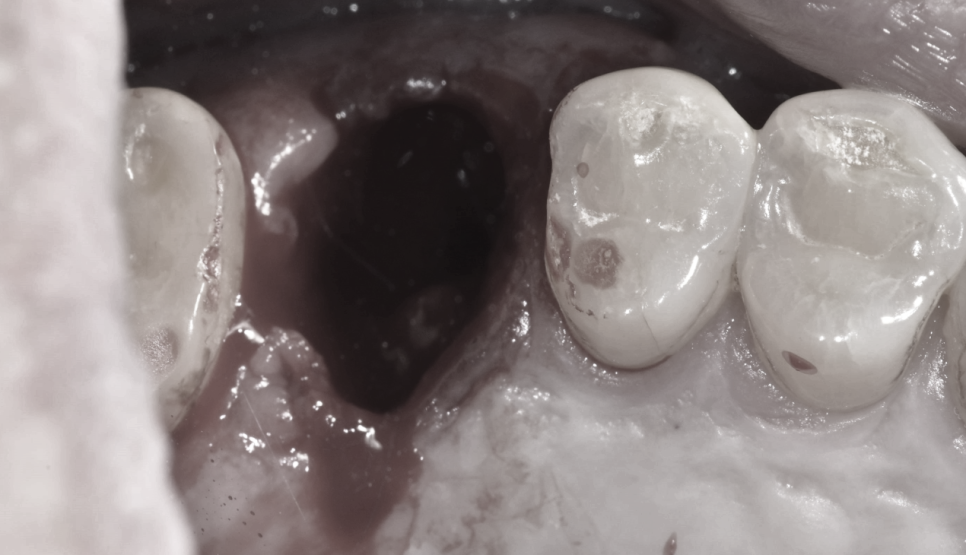

발치를 해보니 치아가 산산조각이 나있습니다.

3개의 뿌리가 삼단 분리되어 발치하였습니다.

문제는... 오래된 염증으로 발치와

이 뽑은 공간이 잇몸뼈 함몰이 일어났다는 것인데요

푹 꺼진거죠

뼈가 없습니다.

임플란트는 뼈가 남아있어야 심고 기다리는 것인데

잇몸뼈 함몰이 일어나서 도저히 당일에 심을 수가 없었습니다.